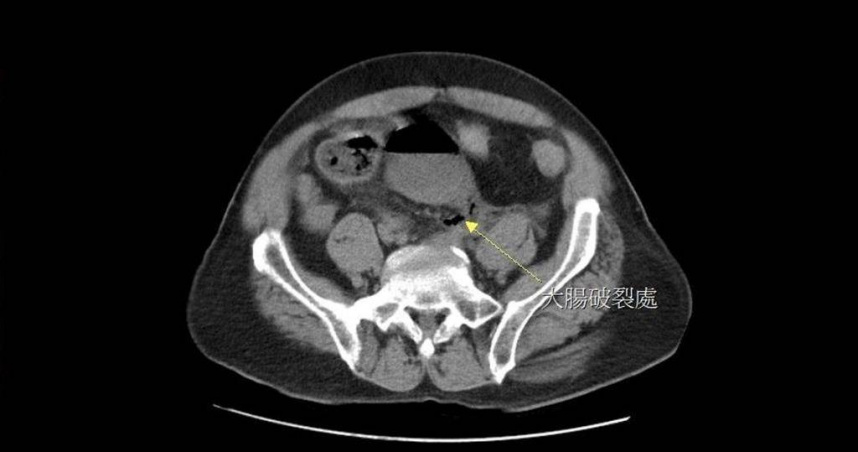

65歲男性病人因嚴重便祕而自行灌腸,導致直腸破洞(箭頭處),引發腹膜炎。(圖/翻攝畫面)

經電腦斷層掃描檢查,醫師發現黃先生直腸上端有一個直徑約2公分的破洞,糞水隨之流入腹腔,引發嚴重腹膜炎。外科部主任馮啟彥緊急進行腹腔鏡手術,發現破洞位置靠近乙狀結腸的轉彎處,研判是因灌腸過度用力造成。手術後,黃先生順利康復,也表示「再也不敢自行灌腸了」。